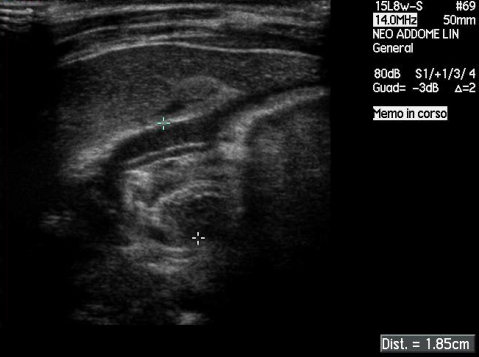

Abbiamo

quindi effettuato un'ecografia dell'addome che ha confermato

l'ipotesi diagnostica documentando un canale pilorico di 22 mm di

lunghezza con spessore della parete muscolare di 4 mm e diametro

totale di 18.5 mm (Figura

2).

Figura 2- Reperto ecografico di stenosi ipertrofica del piloro.

Lo scansione longitudinale del canale pilorico mostra ispessimento della tonaca muscolare (4mm), aumento del diametro complessivo del piloro stesso (18,5 mm) ed aumento della lunghezza del canale (22 mm).